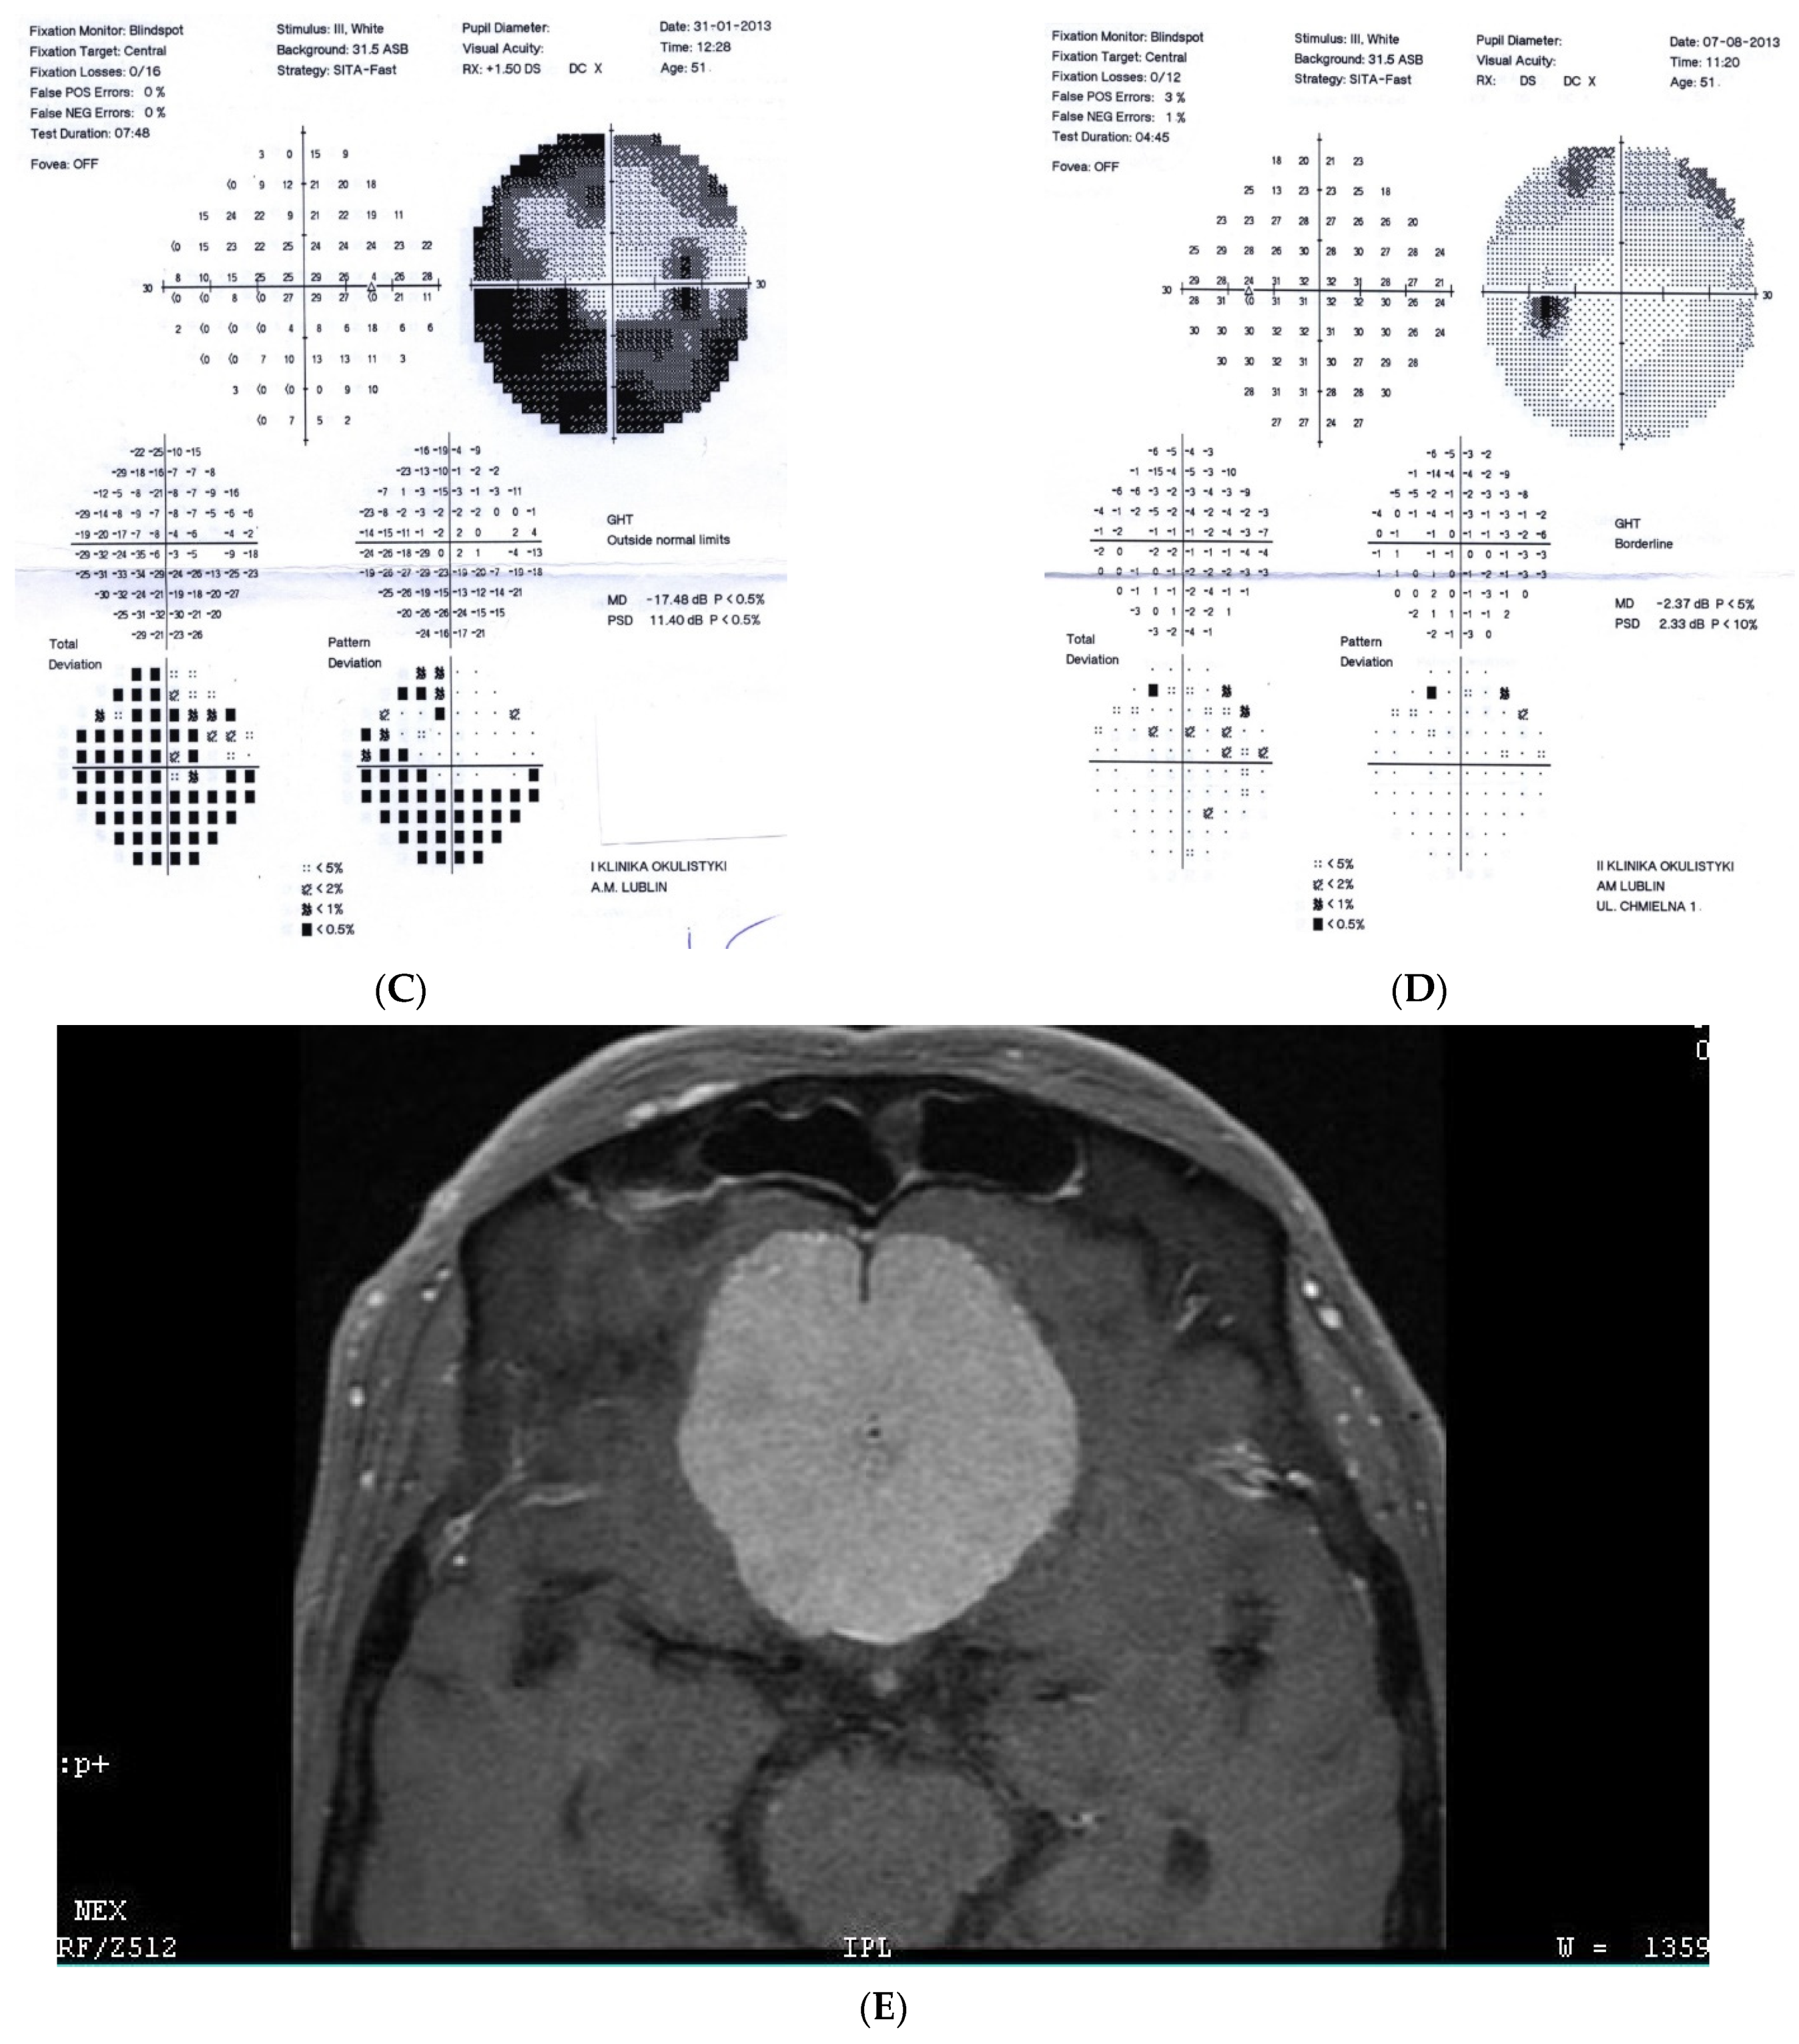

2.2. Case 2

2.5. Case 5